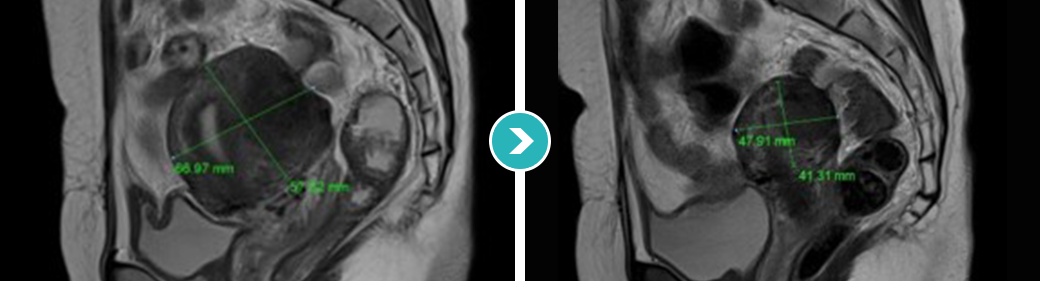

3STEP HIFU PROGRAM 2010년 부터 오직 자궁근종과 자궁선근증의 안전한 치료를 위해 전 과정MRI통합 하이푸 치료 프로그램 운영

시술 후 하이푸 치료 브리핑 및 객관적 평가

MRI촬영으로 자궁근종의 상태(위치, 개수, 크기, 모양 등), 자궁근종의 혈액공급 및 혈류,

자궁근종과 인접한 주요장기 및 구조, 초음파 발사경로의 확보 등을 분석함. 또한, 정밀초음파는 제거할 자궁근종의 개수, 자궁근종의 치료 슬라이스 수와

각 슬라이스의 체적, 근종제거마진, 근종과 인접한 장기와의 상관관계 등을 분석합니다.